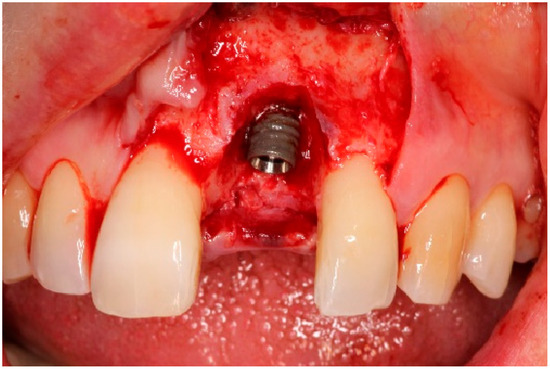

4. Timeline and Diagnostic Assessment

5. Therapeutic Intervention

5.2. Non-Surgical Pre-Treatment

5.3. Surgical Treatment